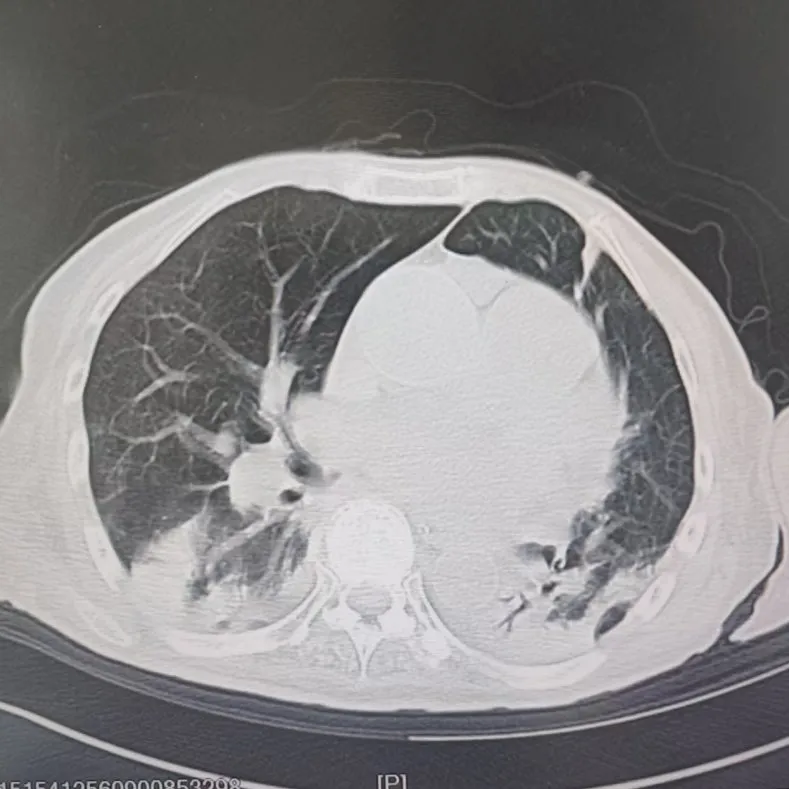

引言 / / Introduction 年近8旬的陳阿姨(化名)因腦梗長(zhǎng)期癱瘓?jiān)诖?,康?fù)期間突然高燒不退,體溫升至39℃,在抗感染過(guò)程中,她并發(fā)高滲性脫水,病情急劇惡化,被緊急送入ICU。此時(shí),她已氣管切開(kāi),依靠呼吸機(jī)維持呼吸,并伴有低蛋白血癥、低鉀高鈉血癥及房顫等多種危重情況,命懸一線! PART. 01 多重泛耐藥菌疊加大量基礎(chǔ)病 治療陷入“死胡同” 呼吸與危重癥醫(yī)學(xué)科及ICU通力協(xié)作,穩(wěn)住患者生命體征。治療過(guò)程中,進(jìn)一步的病原學(xué)檢查結(jié)果令人心驚:陳阿姨的肺部遭遇多種“超級(jí)細(xì)菌”混合侵襲,包括銅綠假單胞菌、鮑曼不動(dòng)桿菌、嗜麥芽窄食單胞菌、金黃色葡萄球菌、木糖氧化無(wú)色桿菌、粘質(zhì)沙雷菌等高度耐藥菌,堪稱(chēng)耐藥菌“大本營(yíng)”。這些細(xì)菌對(duì)常用抗生素幾乎全部耐藥,治療難度高,死亡率高。 治療前患者肺部影像 PART. 02 多學(xué)科強(qiáng)強(qiáng)聯(lián)手 量身定制攻堅(jiān)方案 面對(duì)無(wú)藥可用的困境,呼吸科沒(méi)有放棄!宋剛主任帶領(lǐng)團(tuán)隊(duì)聯(lián)合藥學(xué)部、檢驗(yàn)科、重癥醫(yī)學(xué)科成立多學(xué)科治療組,根據(jù)患者身體情況實(shí)時(shí)調(diào)整用藥,逐一攻破耐藥菌。這場(chǎng)與“超級(jí)細(xì)菌”的拉鋸戰(zhàn)持續(xù)了30多個(gè)日夜。 在醫(yī)護(hù)日夜堅(jiān)守和家屬全力配合下,陳阿姨的感染終于被遏制:高燒退了,肺部陰影消散了!就在即將宣告勝利時(shí),又發(fā)現(xiàn)她存在泌尿感染問(wèn)題,隨即轉(zhuǎn)入泌尿外科協(xié)同治療。當(dāng)宋主任回訪時(shí),看到陳阿姨精神煥發(fā)、體溫平穩(wěn),所有參與救治的人都感慨萬(wàn)分!這場(chǎng)救治,正是呼吸與危重癥醫(yī)學(xué)科攻堅(jiān)耐藥菌硬實(shí)力的生動(dòng)體現(xiàn)! 治療后患者肺部影像 從“無(wú)藥可用”到“絕處逢生”,此次成功救治,集中體現(xiàn)了呼吸與危重癥醫(yī)學(xué)科以耐藥菌精準(zhǔn)診治為核心的學(xué)科特色與技術(shù)優(yōu)勢(shì)。面對(duì)一次次的嚴(yán)峻挑戰(zhàn),科室始終秉持“生命至上、知難而進(jìn)”的信念,以多學(xué)科協(xié)作為平臺(tái),憑借個(gè)體化精準(zhǔn)用藥策略,為患者尋找生機(jī),為更多陷入困境的患者和家庭帶去了實(shí)實(shí)在在的希望。 PART. 03 人民醫(yī)院 人民名醫(yī) 宋剛 主任醫(yī)師 ·葫蘆島市第二人民醫(yī)院呼吸與危重癥醫(yī)學(xué)科主任 ·遼寧省生命科學(xué)學(xué)會(huì)東北呼吸與危重癥醫(yī)學(xué)(PCCM)分會(huì)遼寧省基層委員會(huì)副主任委員 ·遼寧省細(xì)胞生物學(xué)學(xué)會(huì)放射粒子治療專(zhuān)業(yè)委員會(huì)理事 ·遼寧省抗擊新冠肺炎疫情先進(jìn)個(gè)人 ·葫蘆島市勞動(dòng)鑒定委員會(huì)專(zhuān)家?guī)斐蓡T ·葫蘆島市醫(yī)學(xué)會(huì)呼吸內(nèi)科學(xué)分會(huì)第三屆委員會(huì)副主任委員 專(zhuān)業(yè)特色:擅長(zhǎng)呼吸系統(tǒng)疑難及急危重患者的救治,如急慢性支氣管炎、支氣管哮喘、慢性阻塞性肺疾病、肺炎、肺栓塞、肺癌、間質(zhì)性肺疾病、睡眠呼吸暫停綜合征等,尤其擅長(zhǎng)有創(chuàng)無(wú)創(chuàng)機(jī)械通氣、支氣管鏡下相關(guān)檢查及治療(TBNA、氣道支架置入術(shù)、球囊擴(kuò)張等)、全肺灌洗術(shù)等領(lǐng)先技術(shù),發(fā)表國(guó)家級(jí)期刊多篇。